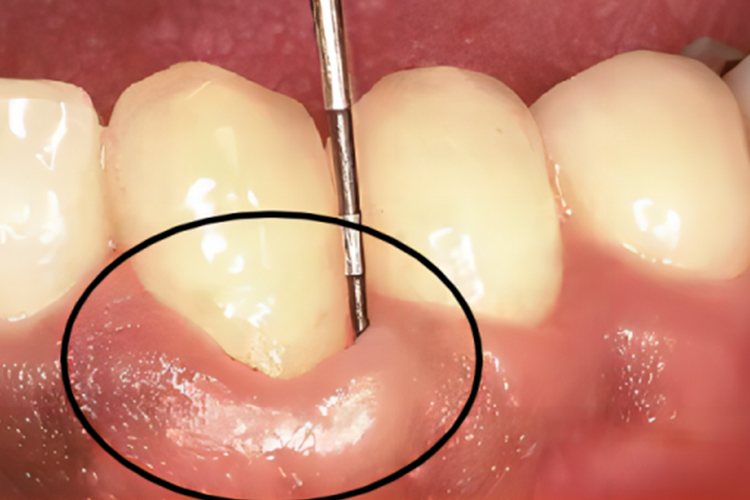

牙周袋是指龈沟病理性加深后,在牙根与牙龈之间形成的开口于冠方的盲袋,内含有菌斑、软垢、龈沟液、食物残渣、脱落上皮等。牙周袋牙龈外观呈暗红色、质地松软、牙龈表面光亮、点彩消失,探诊后会有出血,可伴有疼痛、袋内溢脓等。

牙周袋是由于牙周组织炎症引起的牙周膜胶原纤维破坏和结合上皮的根方增殖所导致,慢性炎症是主要病因。